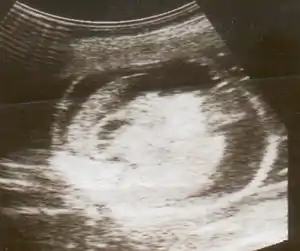

| An ultrasound featuring a baby with Hydrops fetalis | |

تشخیص هیدروپس فتالیس از طریق سونوگرافی قابل تشخیص میباشد.